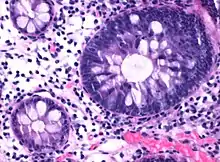

Tubular adenoma

In constrast to hyperplastic polyps, these display dysplasia.